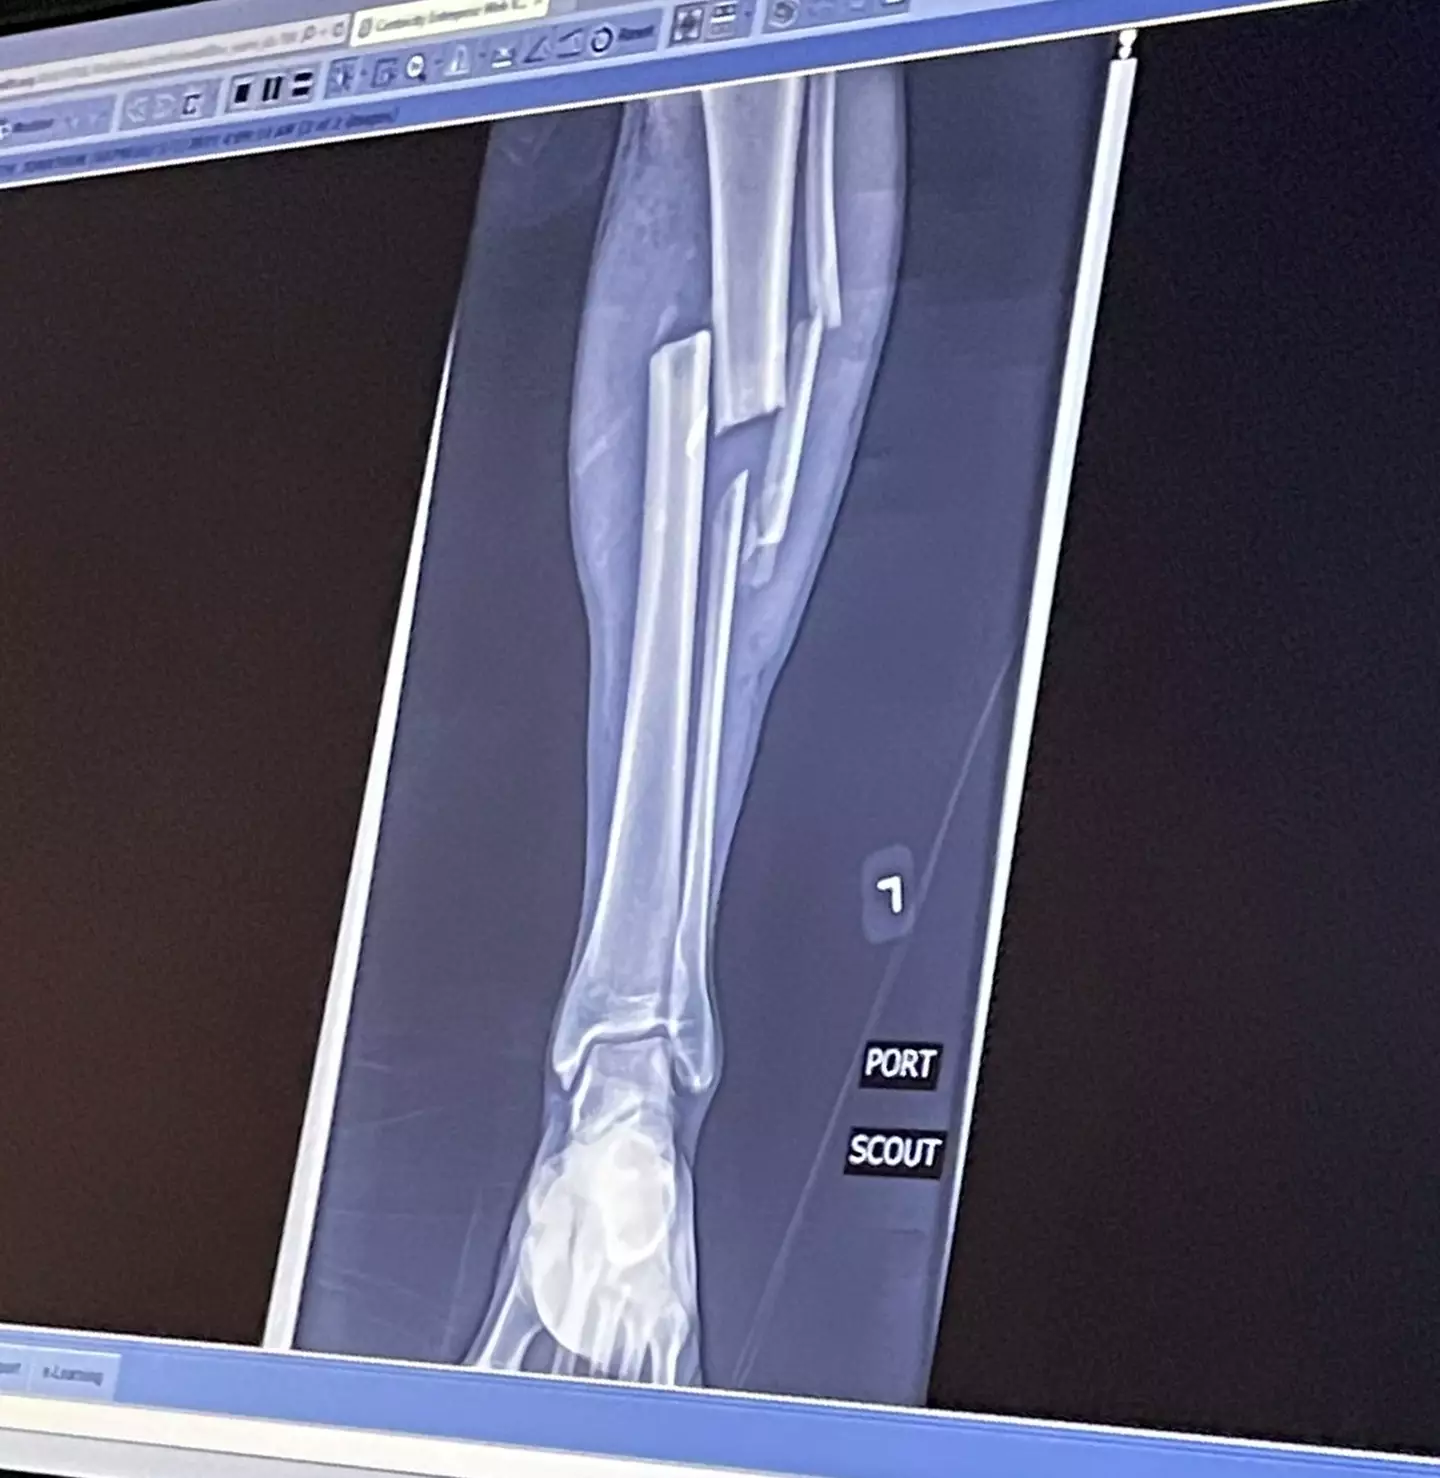

He was rushed to hospital where he was treated for numerous injuries, including two caved in shins, which were so bad the bones had pushed through the skin, and broken bones on both knees.

He also fractured his skull, broken both eye sockets, his nose, his jaw and three ribs.

The most severe injuries were in his legs and his crushed right hand, and his ring, middle and pinkie fingers, as well as part of his palm, were all amputated.

He later had his lower right leg amputated after he was warned he would need up to 12 more surgeries to try and save it.